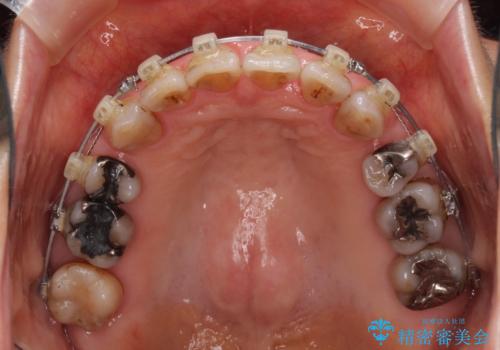

- 矯正装置

- クリアブラケット

- 2年7ヶ月

- 突出した口元を引っ込めることを希望して来院された患者様です。

上下左右第一小臼歯4本を抜歯して、口元を改善するワイヤー矯正を行うこととしました。